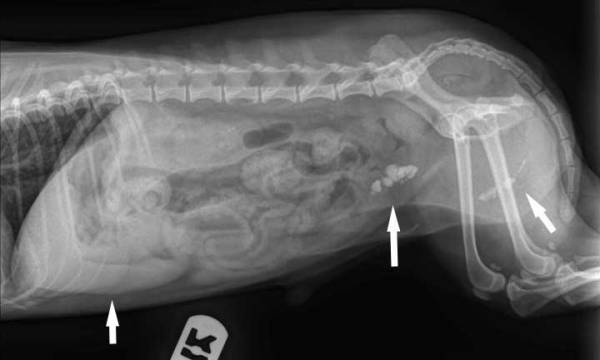

В першу чергу необхідно здати аналізи сечі – клініку і біохімію. Іноді цього достатньо, щоб визначити відсутність/наявність конкрементів і тип каменів. Але в будь-якому випадку ветеринар повинен провести УЗД – це потрібно, щоб підтвердити діагноз та оцінити стан нирок, сечового міхура і жовчовивідних проток. Іноді камені в сечовому у собаки не вдається виявити методом УЗД, тому краще відразу зробити рентген. Ці три дослідження – аналіз сечі, УЗД та рентген, – є основними методами діагностики, без яких неможливо призначити правильне лікування (хіба що пощастить «навмання»).